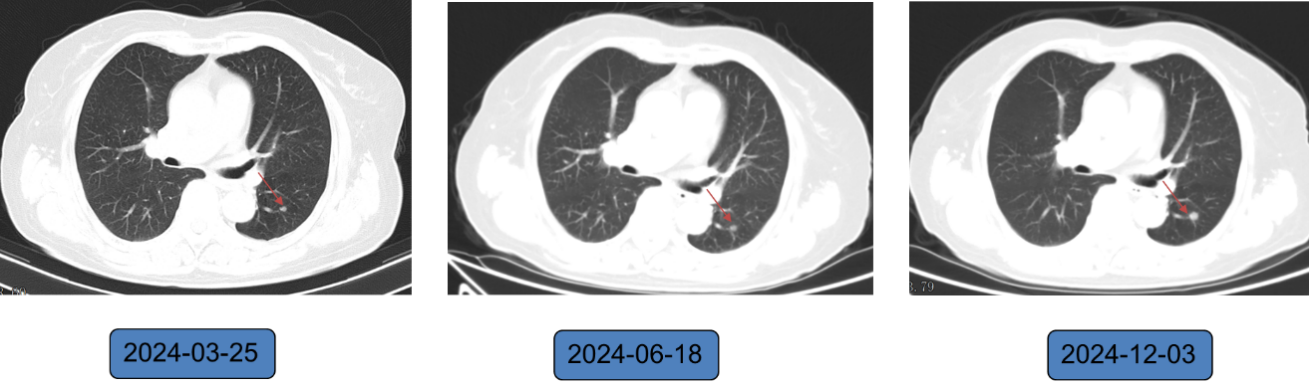

调整治疗方案:2021年7月2日起改用口服长春瑞滨软胶囊(80mg d1、d8/q3w)+吡咯替尼(400mg qd)治疗,共 58 周期,末次治疗时间 2024 年 11 月 28 日。

疗效:2021 年 9 月复查示右乳肿块消失,2023 年 3 月起双侧腋下未探及肿大淋巴结,最佳疗效达 CR;截至 2024 年 11 月,持续维持 CR 状态,PFS 长达 40.9个月。

影像学结果(右乳软组织+肺结节)如下图所示:

图3 影像学变化(1)

图4 影像学变化(2)